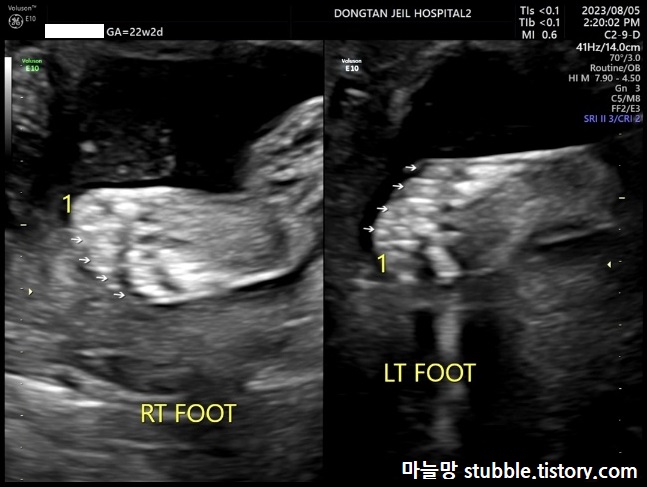

(2) 발가락 개수 확인

발가락 개수를 세어 봅니다.